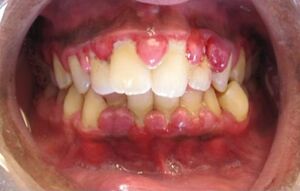

حالة التهاب لثة حادة. | |

The symptoms of gingivitis are somewhat non-specific and manifest in the gum tissue as the classic signs of inflammation:

- Swollen gums

- Bright red or purple gums

- Gums that are tender or painful to the touch

- Bleeding gums or bleeding after brushing and/or flossing

- Bad breath (halitosis)